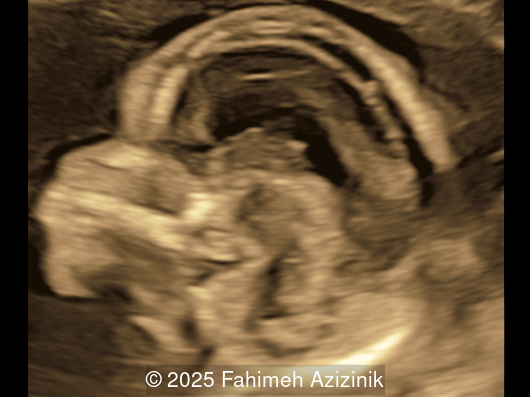

Image 6

Image 7

• Bicoronal craniosynostosis

• Hypertelorism

Bicoronal synostosis is the characteristic cranial hallmark of Apert syndrome, detectable sonographically from 18 weeks. Its most recognizable manifestation is turribrachycephaly, defined by an elevated cephalic index (typically >85–90%) and a tall cranial vault with marked frontal bossing [19]. On prenatal ultrasound, the face in Apert syndrome shows midface hypoplasia with a depressed nasal bridge, proptosis, hypertelorism, and frontal bossing. The extremities demonstrate syndactyly of both bone and soft tissue of the hands and feet with partial-to-complete fusion often involving second, third, and fourth digits, known as “mitten hands” and “socked feet”. In severe cases, all digits are fused, with the presence of a single nail known as “synonychia” [20]. Other ultrasound findings include mild ventriculomegaly, agenesis of the corpus callosum, deficient or absent septum pellucidum, and fusion of the cervical vertebrae at the level of C5-C6 [21]. Cardiovascular (atrial and ventricular septal defect) and genitourinary anomalies (hydronephrosis, and cryptorchidia) are present in 10% of patients [22]. Increased nuchal translucency in the first trimester [23], widely open metopic suture [24], and polyhydramnios [25] have also been reported. Three-dimensional (3D) ultrasound facilitates assessment of surface abnormalities of the face and extremities, and magnetic resonance imaging (MRI) can be used to evaluate associated intracranial conditions [26].